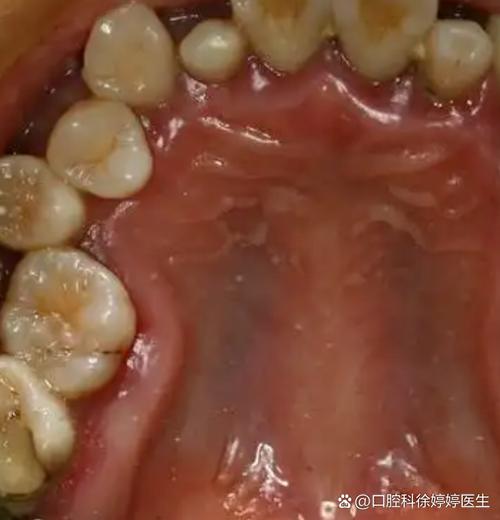

- 口腔卫生不佳:矫正期间牙齿清洁难度增加,若刷牙不彻底,食物残渣堆积形成牙菌斑和牙结石,引发牙龈炎、牙周炎,进而导致支持组织破坏,牙齿松动。

- 口腔卫生是核心:矫正期间食物易嵌塞,建议每次进食后立即漱口,早晚使用含氟牙膏刷牙,配合牙线清除邻面菌斑,必要时使用正畸专用牙刷(如U形刷、正畸刷头)。